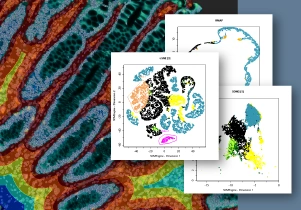

11 Sep, 2024

A Glimpse into StrataQuest 8: Spatial Analysis in Colorectal Cancer

The newest StrataQuest supports in-depth neighborhood analysis with exportable data for statistics. It includes manifold learning (t-SNE, UMAP, SONG), violin plots, 3D diagrams, and other tools that give full control of data.